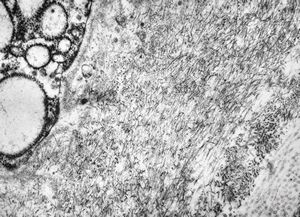

M,1y. | unusually cup-shaped mitochondria - plexus papilloma

M,1y. | intramitochondrial inclusion - plexus papilloma